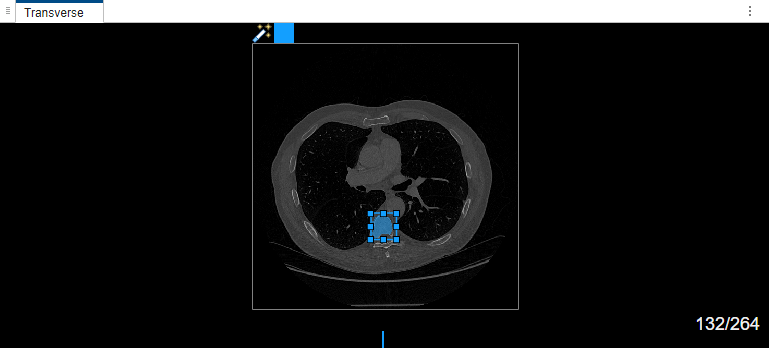

Select label Type1. Draw a bounding box around the object to segment in the transverse plane of the volume.

Once the MedSAM algorithm extracts the embeddings of the image, you can adjust the bounding box.

The MedSAM algorithm segments the object in the bounding box and labels it.